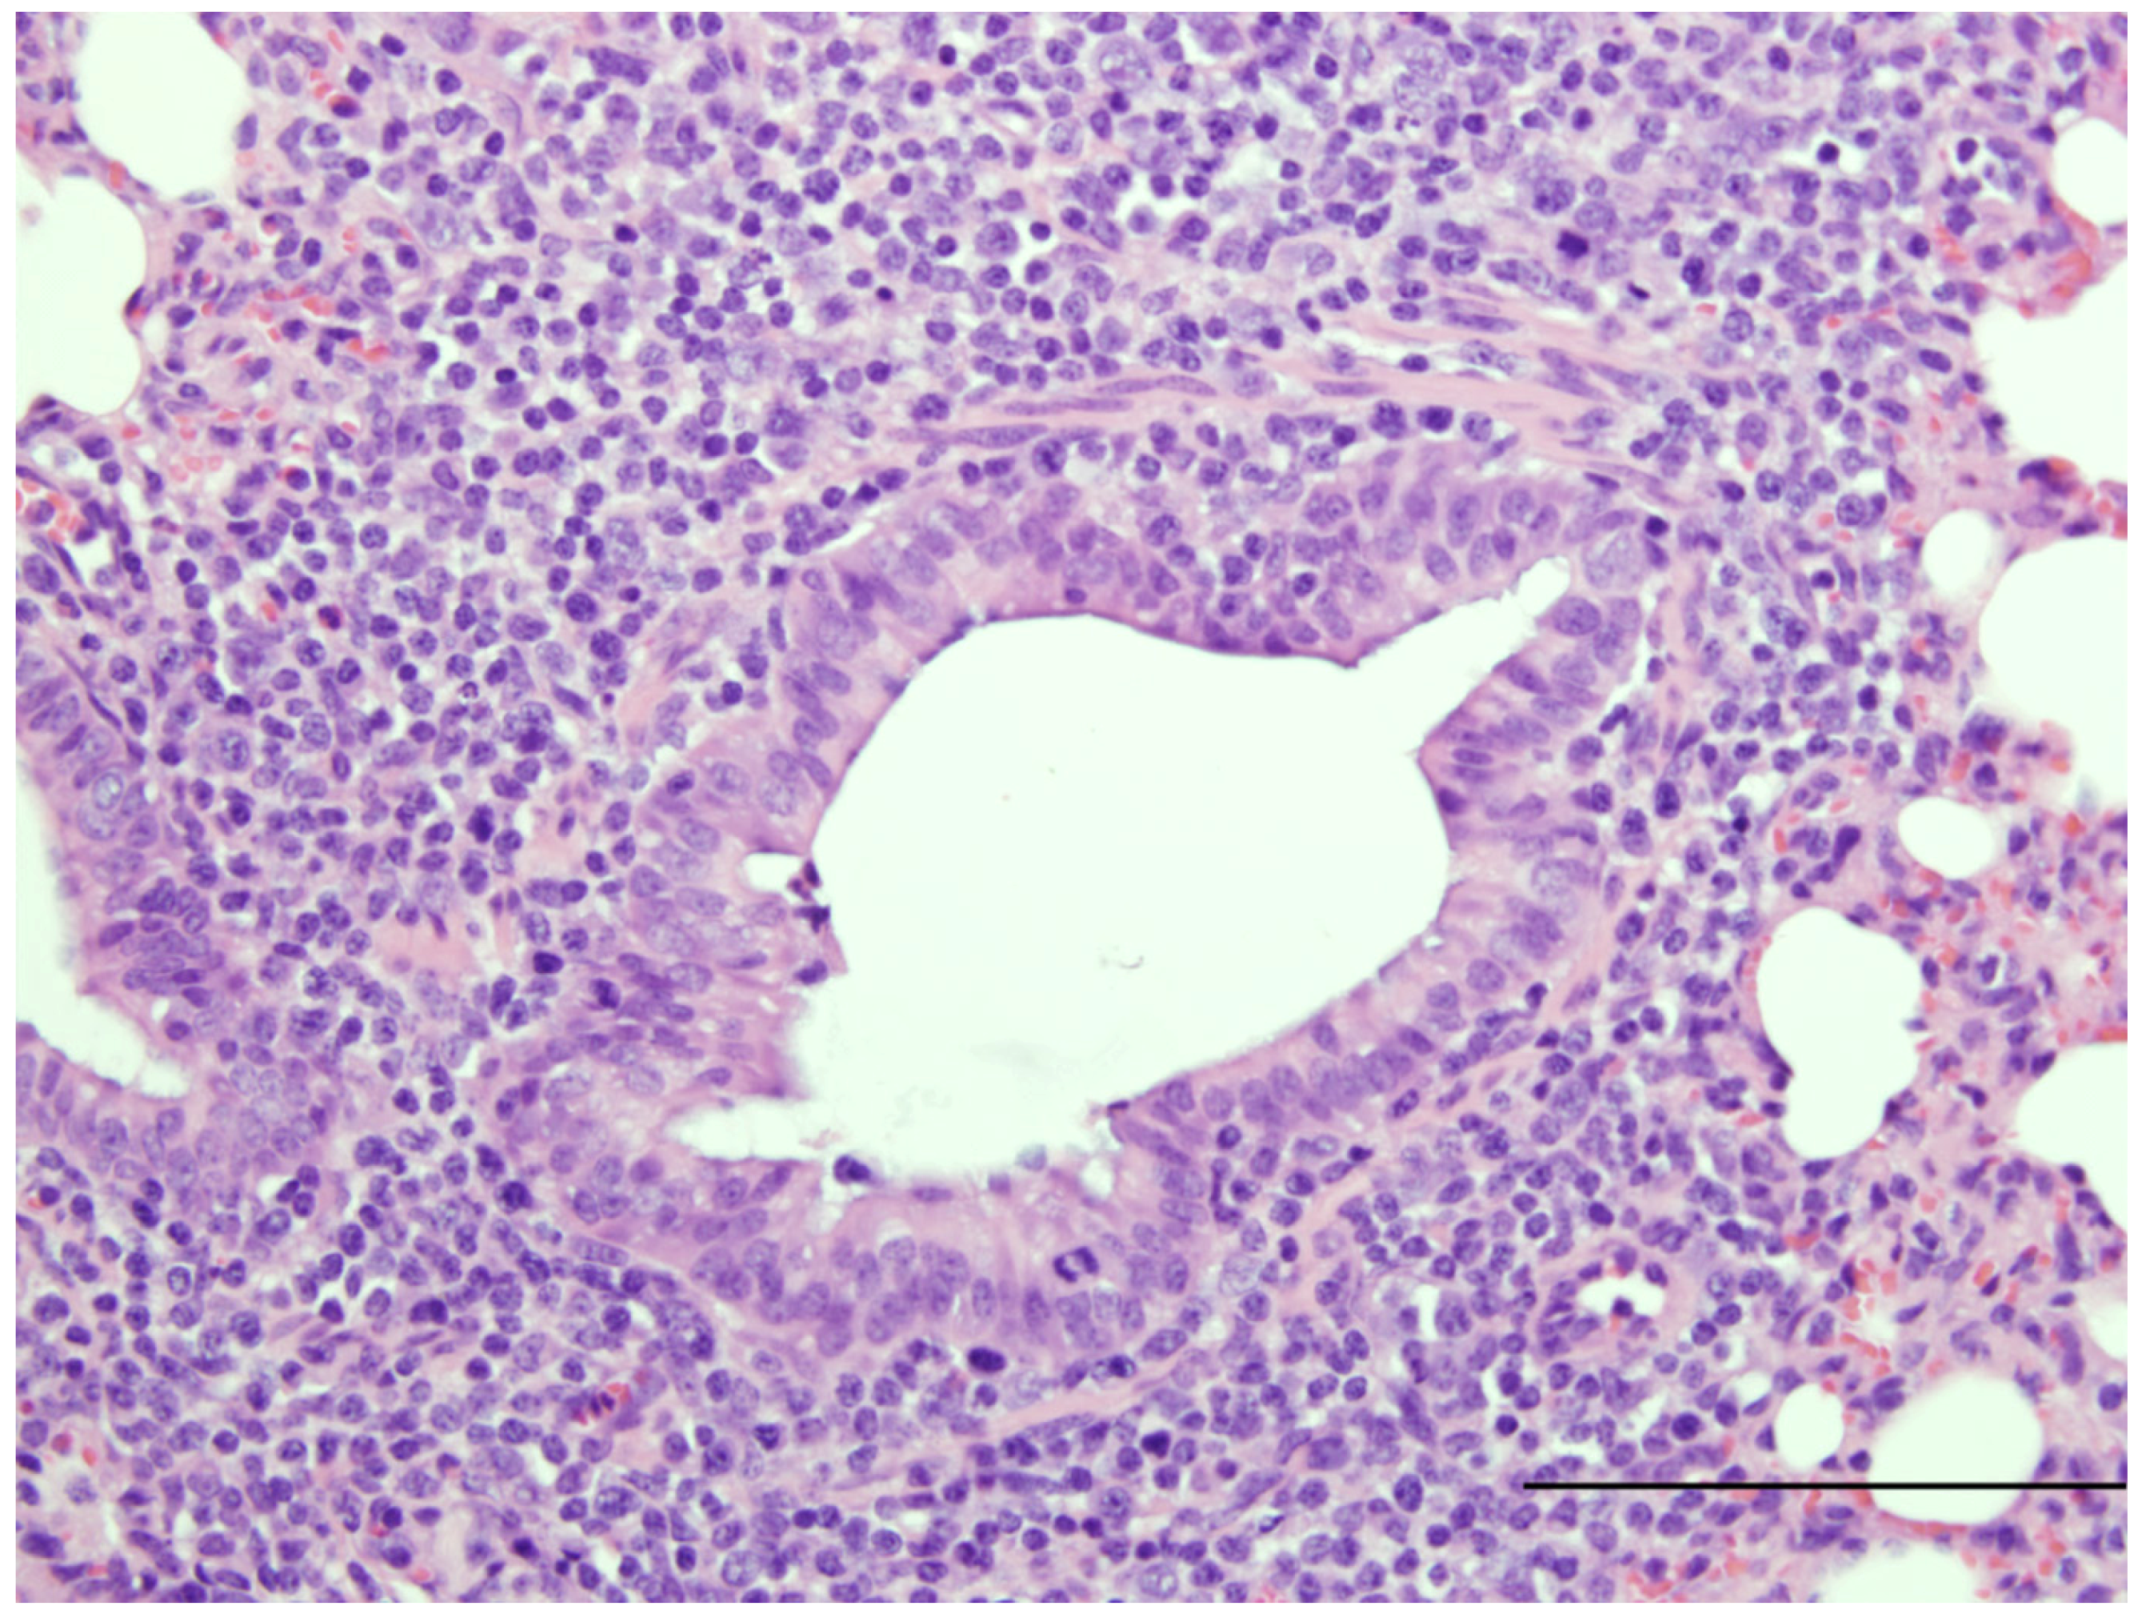

| Susceptible to human RSV strains | Similar to infants | [16,20] Figure 1 |

| Syncytial cell formation | [19,20] Figure 1 | |